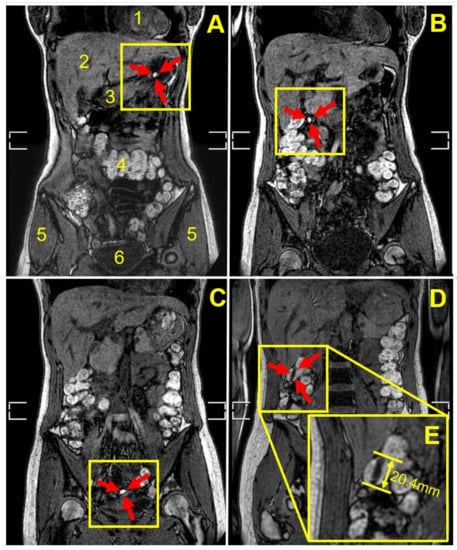

| Participant | Weight Gain (mg) a | Weight Gain Per Surface Area (mg/mm2) | Gastrointestinal Location and Integrity of the Capsule at the Different Imaging Time Points (min) | |||||||

|---|---|---|---|---|---|---|---|---|---|---|

| 45 | 90 | 135 | 180 | 225 | 270 | 315 | 360 | |||

| 1 | 9.2 ± 0.8 | 0.02 | Stomach | Stomach | Stomach b | NO c | NO | NO | NO | NO |

| 2 | 18.2 ± 1.2 | 0.04 | Stomach | Stomach | Duodenum | Duodenum | Term ileum | NO | NO | d |

| 3 | 18.2 ± 1.2 | 0.04 | Stomach | Stomach | Term ileum | Asc colon | Hep flexure | Hep flexure | Hep flexure | Hep flexure |

| 4 | 18.2 ± 1.2 | 0.04 | Stomach | Jejunum | Jejunum | Jejunum | Term ileum | Term ileum | Term ileum | NO |

| 5 | 18.2 ± 1.2 | 0.04 | Stomach | Jejunum | Cecum | Cecum | Asc colon | Asc colon | NO | Hep flexure |

| 6 | 18.2 ± 1.2 | 0.04 | Stomach | Stomach | Term ileum | Term ileum | NO | NO | NO | NO |

| 7 | 18.2 ± 1.2 | 0.04 | Stomach | Jejunum | Jejunum | Term ileum | Term ileum | NO | NO | NO |

| 8 | 36.0 ± 5.2 | 0.08 | Stomach | Jejunum | Term ileum | Cecum | NO | NO | shade | |

| 9 | 52.6 ± 9.7 | 0.11 | Stomach | Duodenum | Term ileum | Hep flexure | Hep flexure | Trans colon | Trans colon | |

| 10 | 52.6 ± 9.7 | 0.11 | Stomach | Stomach | Duodenum | Duodenum | NO | NO | ||